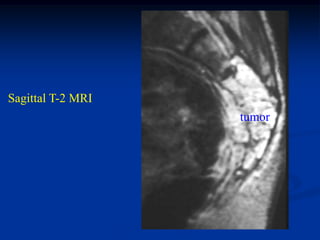

Sagittal T-1 MRI

shows recurrent tumor

above ankle